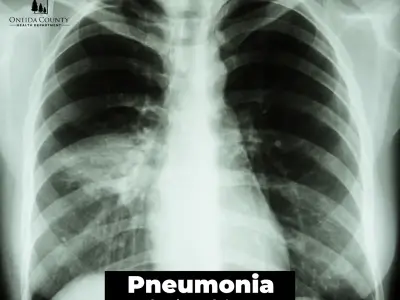

Understanding pneumonia and its main causes

Uncover the facts about pneumonia. This expert guide explains the causes (bacterial, viral, fungal), key symptoms, and prevention tips for this serious lung infection.